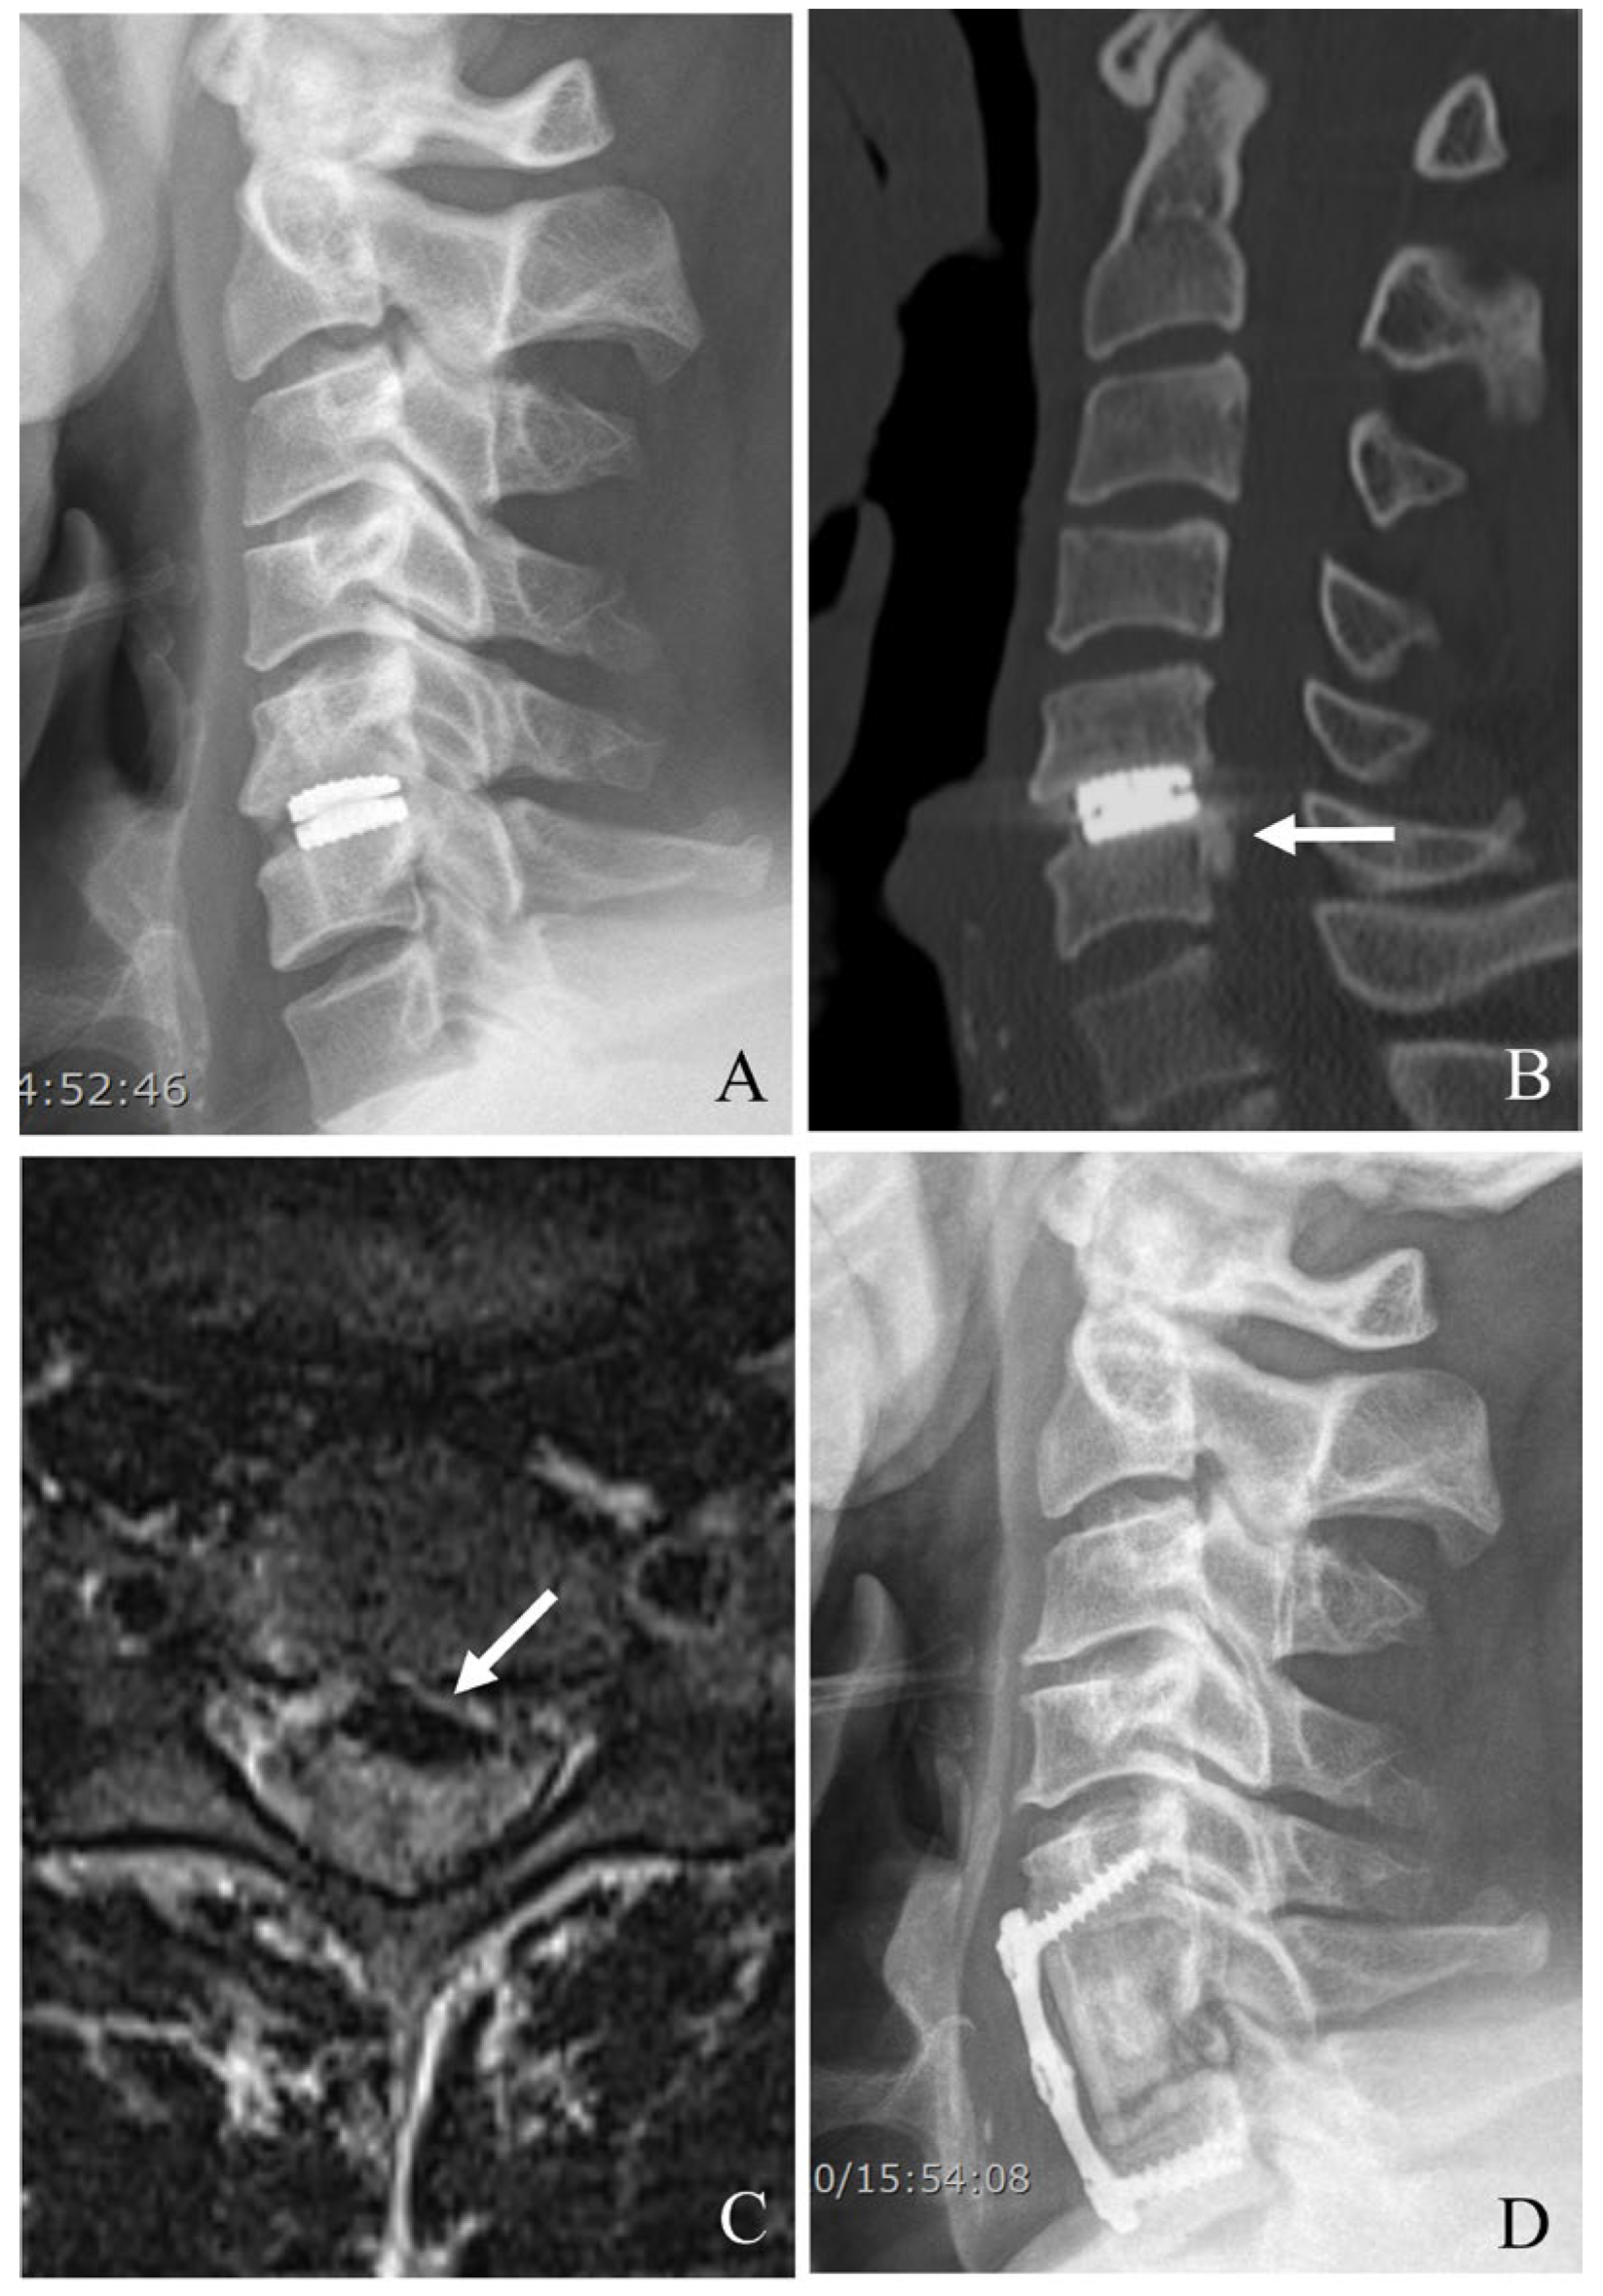

Figure 2. Plain X-rays (A), computed tomography (B), and magnetic resonance image (C) showing cervical disc arthroplasty at C5–6 and ossification of the posterior longitudinal ligament (OPLL) of C6 body (white arrow) causing cord compression. The patient underwent removal of the C5–6 prosthesis and OPLL and anterior cervical corpectomy and fusion (D).

For ACDF, after device removal, the intervertebral space is prepared for fusion. A structural graft (autograft, allograft, or synthetic cage) is placed, followed by anterior plating to provide immediate stability. In cases of severe bone loss or multilevel involvement, a corpectomy may be required, with the placement of a cage or graft to restore anterior column support for ACCF (Figure 2). The decision between two-level ACCF and three-level ACDF must be individualized based on the patient’s pathology, bone quality, and sagittal alignment needs. While corpectomy provides better deformity correction, it carries higher surgical risk and requires more extensive stabilization. In contrast, three-level ACDF is less invasive but has higher rates of pseudarthrosis, potentially leading to revision surgery. Understanding these nuances allows for more tailored surgical planning and improved patient outcomes [31,32].